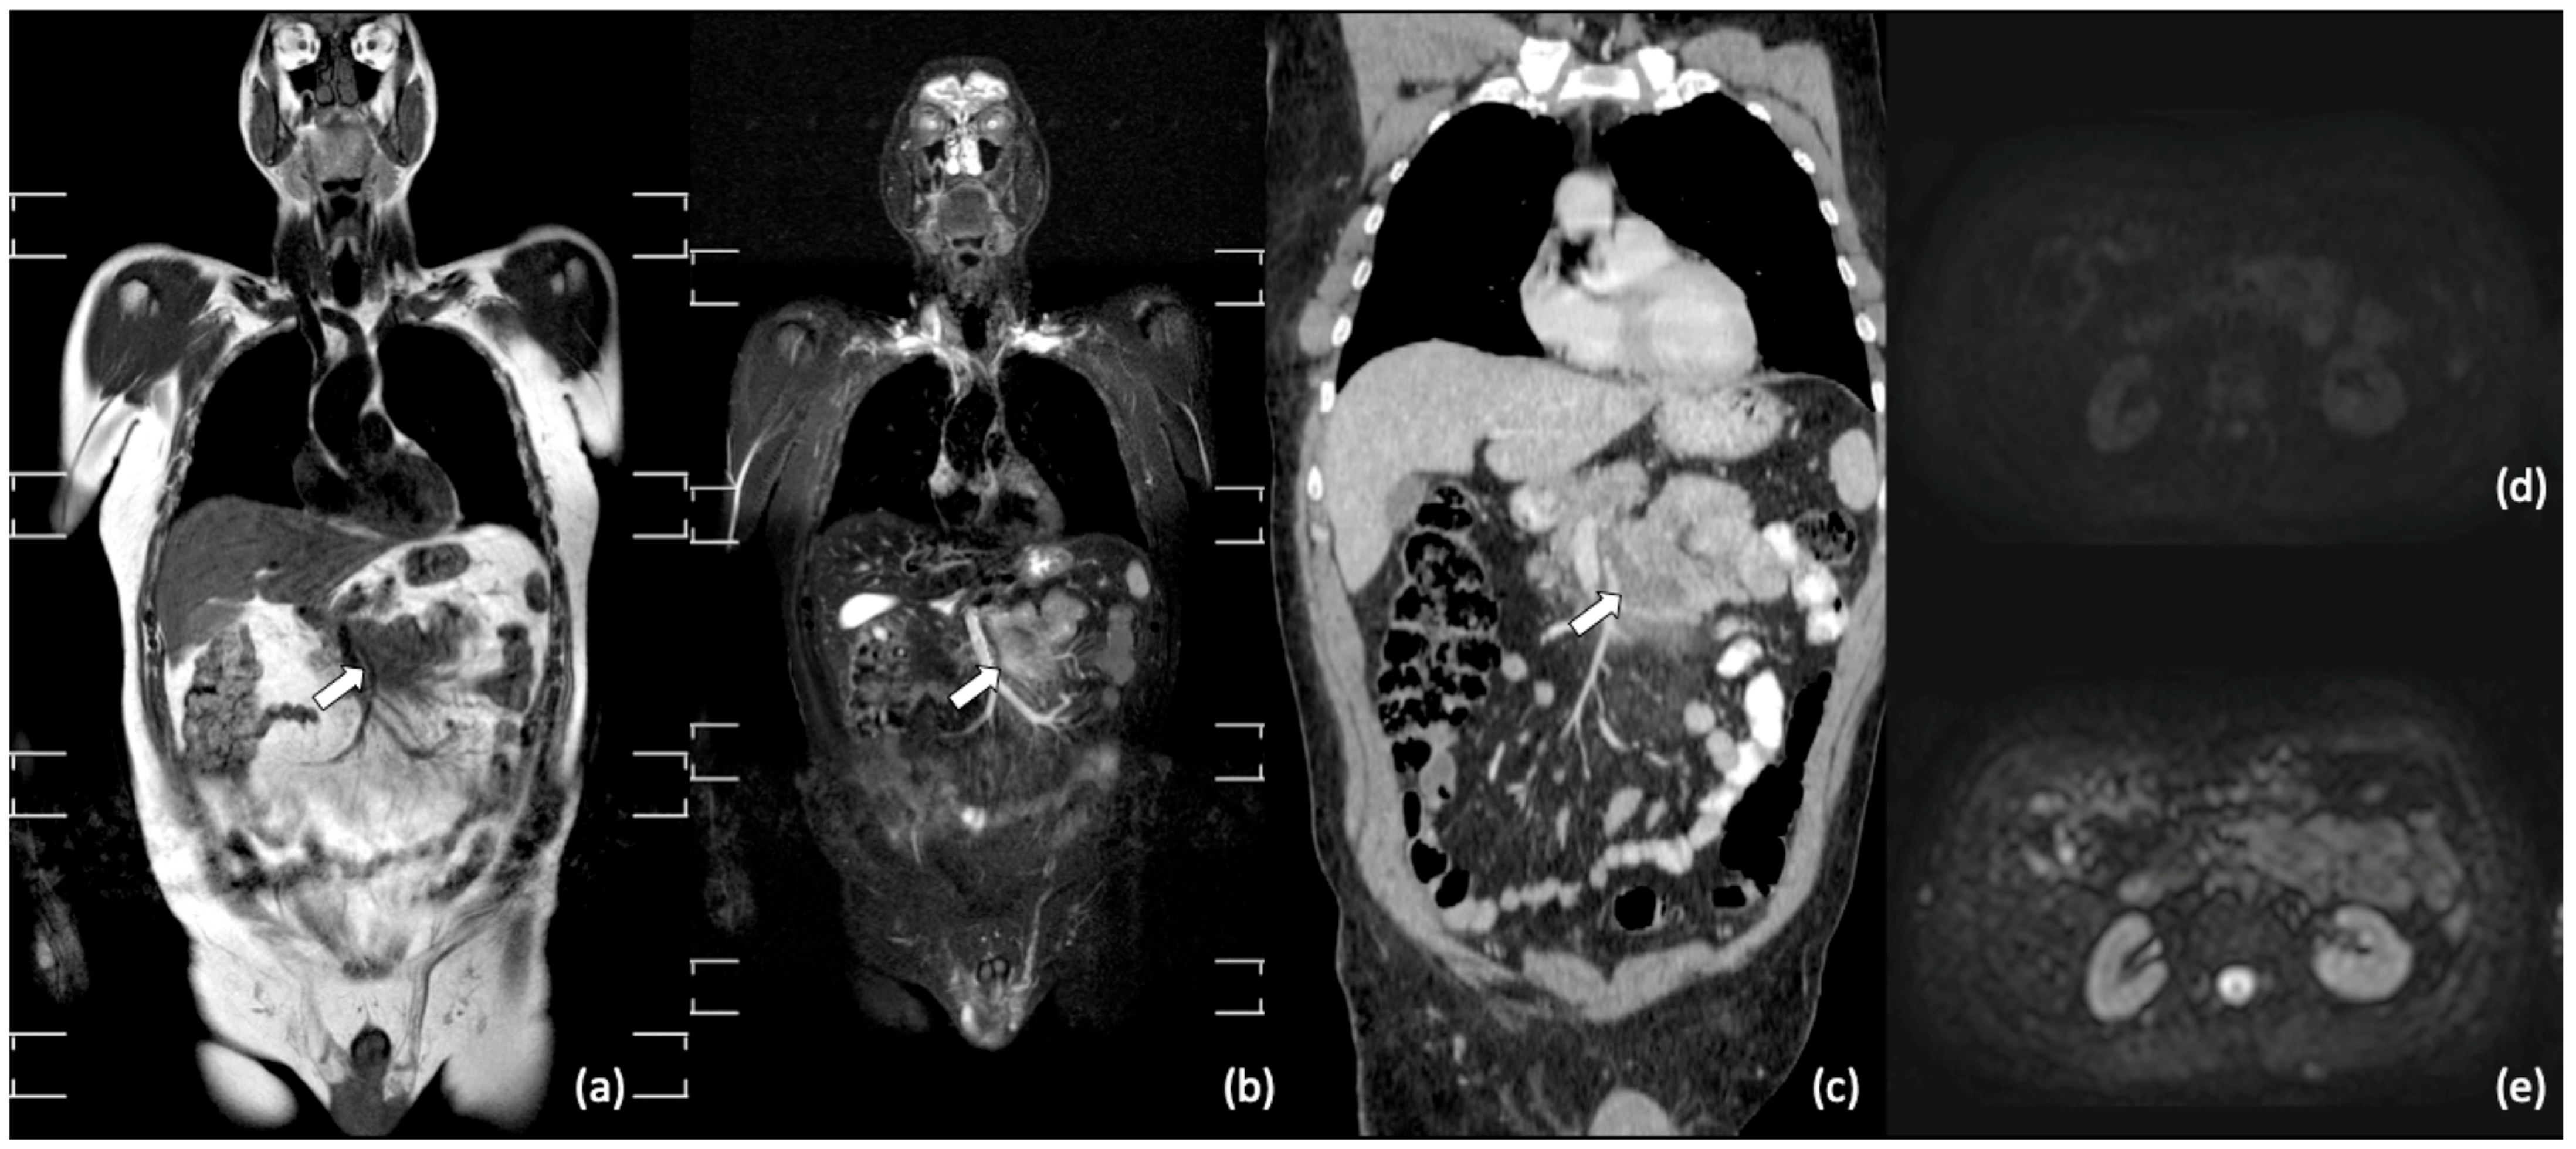

- Stecco, A.; Buemi, F.; Quagliozzi, M.; Lombardi, M.; Santagostino, A.; Sacchetti, G.M.; Carriero, A. Staging of Primary Abdominal Lymphomas: Comparison of Whole-Body MRI with Diffusion-Weighted Imaging and18F-FDG-PET/CT. Gastroenterol. Res. Pr. 2015, 2015, 1–8. [Google Scholar] [CrossRef] [PubMed]

- Albano, D.; Patti, C.; Lagalla, R.; Midiri, M.; Galia, M. Whole-body MRI, FDG-PET/CT, and bone marrow biopsy, for the assessment of bone marrow involvement in patients with newly diagnosed lymphoma. J. Magn. Reson. Imaging 2017, 45, 1082–1089. [Google Scholar] [CrossRef]

- Kwee, T.C.; Vermoolen, M.A.; Akkerman, E.A.; Kersten, M.J.; Fijnheer, R.; Ludwig, I.; Beek, F.J.; van Leeuwen, M.S.; Bierings, M.B.; Bruin, M.C.; et al. Whole-body MRI, including diffusion-weighted imaging, for staging lymphoma: Comparison with CT in a prospective multicenter study. J. Magn. Reson. Imaging 2014, 40, 26–36. [Google Scholar] [CrossRef]